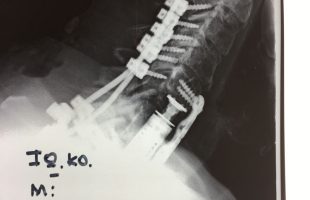

Η Μα. Φο. 26 ετών προ δεκαετίας υποβλήθηκε (αλλαχού) σε χειρουργική επέμβαση στη θωρακο-οσφυική περιοχή της σπονδυλικής στήλης (Σ.Σ.). Η επέμβαση εγένετο προκειμένου να αφαιρεθεί καλοήθης νεοπλασματική εξεργασία (επενδύμωμα) η οποία της είχε προκαλέσει σφιγκτηριακές και νευρολογικές διαταραχές στα κάτω άκρα. Προκειμένου να γίνει εξαίρεση της νεοπλασματικής βλάβης, πραγματοποιήθηκε ευρεία αφαίρεση οπίσθιων στηρικτικών στοιχείων τωνRead more →